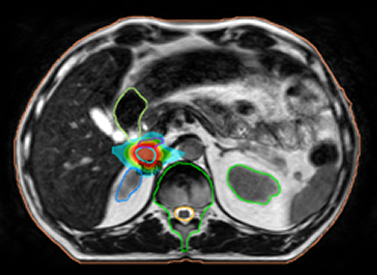

MR-guided SBRT for small adrenal gland metastases

Certainty to deliver SBRT to small soft tissue targets accurately and efficiently with 2 mm margins

Accounting for motion whilst delivering the beam is made possible by True Tracking. It continuously tracks the 3D position of any target non-invasively and in real-time. Four strategies can be used for rapid beam gating.

True Tracking enables the system to move the beam rapidly to compensate for a sustained intrafraction drift. This means when a target moves, the treatment can be adapted without the time penalty of acquiring another 3D image.